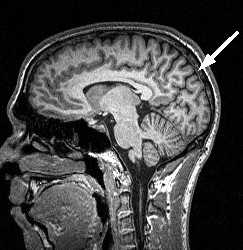

МРТ головного мозга. Срединный сагиттальный срез. Намёт мозжечка (стрелка).

Выше намёта расположены полушария мозга. Каждое полушария мозга состоят из четырёх долей - лобной, теменной, затылочной и височной. Если патология расположена в полушарии, то надо решить к какой доле оно относится. Для этого сперва надо найти борозды, служащие границами долей.

Центральная борозда (sulc.centralis) лучше видна в сагиттальной плоскости. Она расположена по середине между параллельными ей прецентральной и постцентральной бороздами. Существует много вариантов строения и хода борозды. Обычно она имеет значительную протяжённость и идёт в передне-нижнем направлении от межполушарной щели к Сильвиевой щели, которой достигает не всегда. Нижний конец борозды, либо продолжается в основном её направлении, либо загибается назад. Центральная борозда может прерывается по ходу. В поперечной плоскости на верхних срезах борозда имеет наибольшую протяжённость, доходя почти до межполушарной щели. Чем ниже срез, тем короче на нём центральная борозда. На уровне боковых желудочков она едва прослеживается . Центральная борозда разграничивает лобную и теменную доли .

МРТ головного мозга. Латеральный сагиттальный срез. Центральная борозда (стрелка).